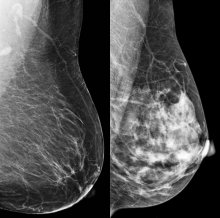

BCAC Chair Libby Burgess reflected on this question after attending the premier international breast cancer research conference, SABCS 2023, in San Antonio Texas last month. Triple negative breast cancer (TNBC) is an aggressive subtype lacking HER2 or hormone receptors. It is the most challenging type of breast cancer to treat, particularly at the advanced stage. However, research over the last 20 years has broadened treatment options and improved patient outcomes.